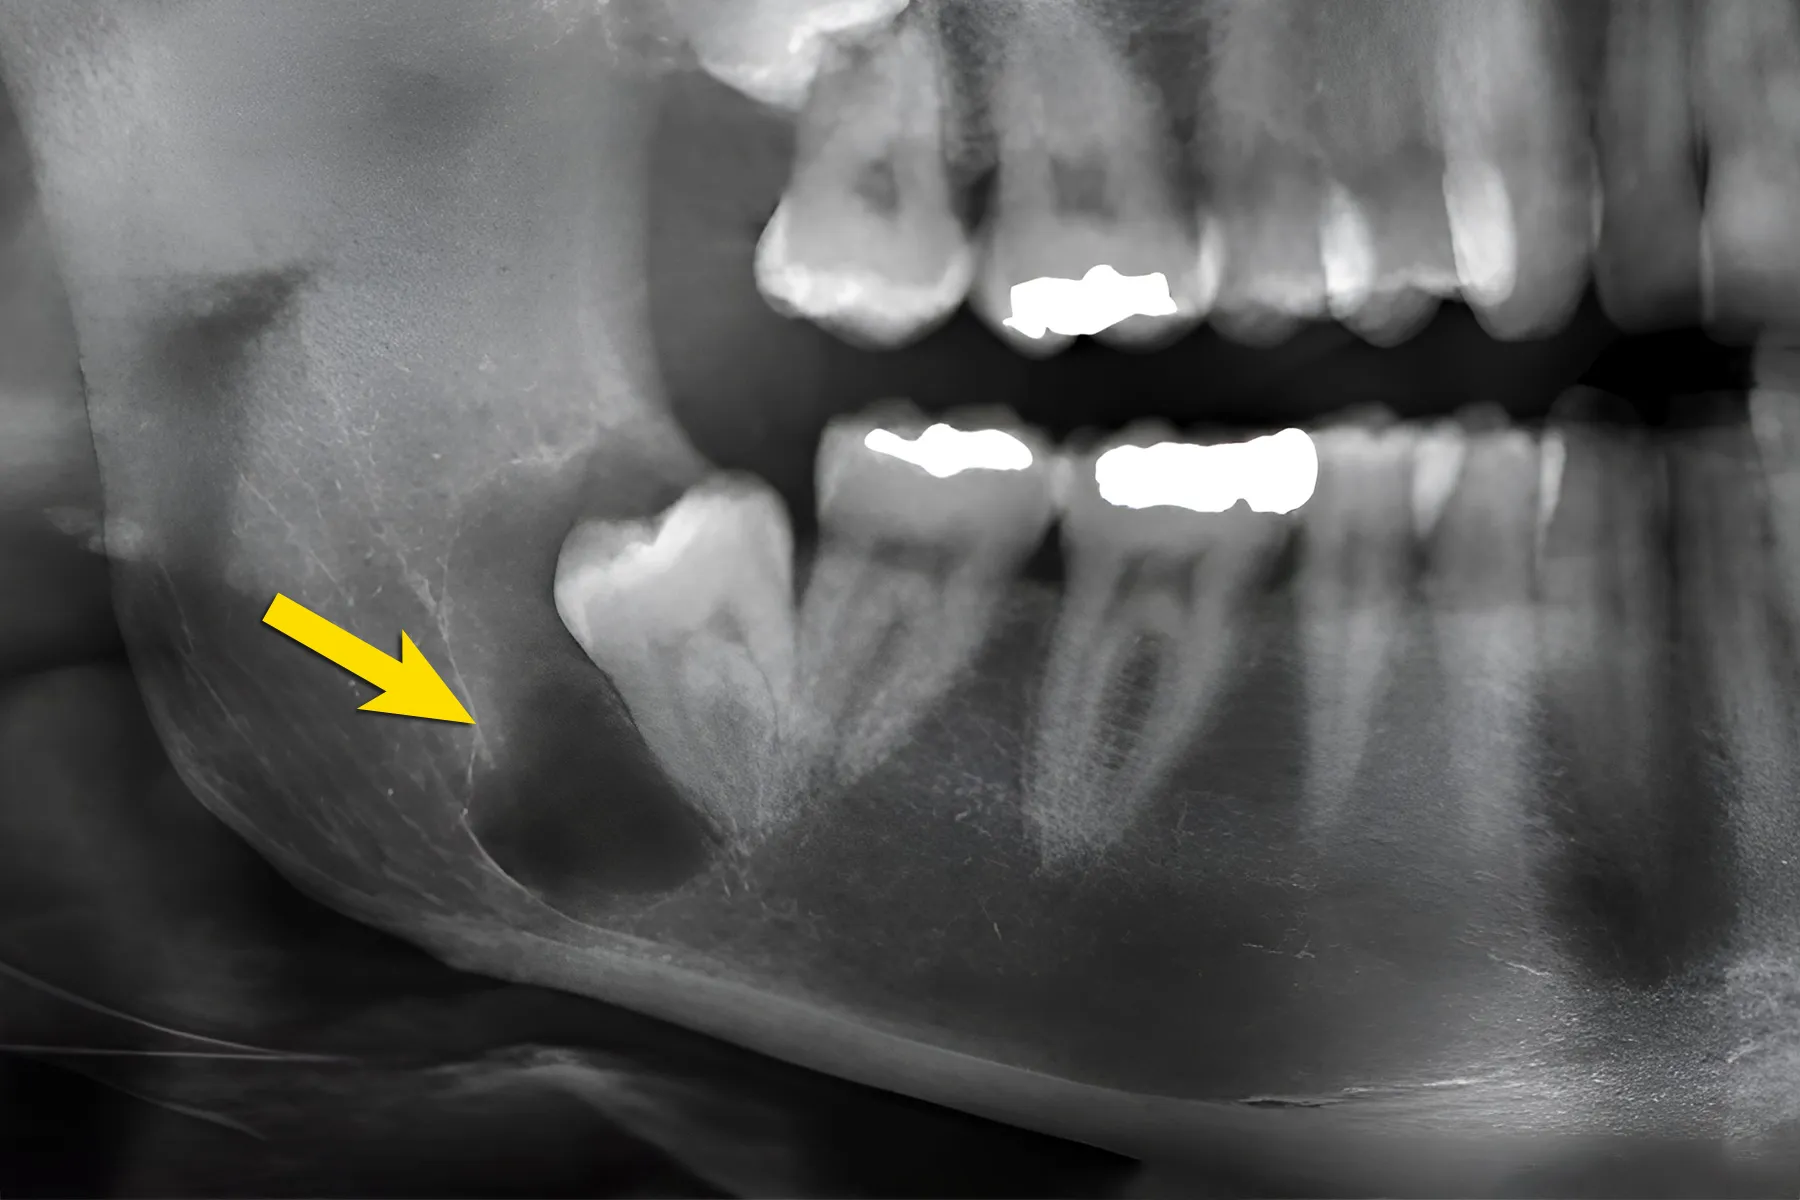

+ Giai đoạn thầm lặng: Kéo dài hàng năm, lâm sàng không có gì đặc biệt, khám thấy thiếu một răng, răng sữa vẫn còn tồn tại, lung lay ít hoặc nhiều. X-quang thấy một vùng thấu quang tròn, rõ, quanh một thân răng ngầm ở phía trên. Đôi khi rất khó phân biệt hình ảnh nang hay chỉ là một bọc quanh thân răng giãn ra.

+ Giai đoạn sau : Khi nang đã to, biểu hiện bằng một khối u cứng làm phồng ngách lợi, hoặc cả rãnh mũi – má nhưng vẫn không đau, da- niêm mạc bình thường, nếu vị trí nang phía hàm ếch làm hàm ếch bị phồng. Khi nang tiếp tục to làm xương hàm bị tiêu và mỏng đi, khi đó sờ ở ngách lợi có dấu hiệu bóng bàn. X-quang có hình nang và răng ngầm thân quay vào lòng nang.